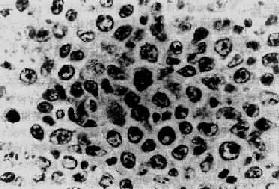

临床病理联系 多数患者起病缓慢,早期多无症状。主要表现为无痛性淋巴结肿大。晚期病变可累及多处淋巴结或其他器官。根据受累的器官不同可引起不同的症状。NHL的扩散途径与HD不同,多无一定规律。晚期病人常有发热、盗汗、消瘦及肝、脾肿大。 儿童淋巴瘤与成人淋巴瘤有些不同,淋巴结外器官的淋巴瘤比较多见。曲折核T细胞淋巴瘤伴纵隔肿块者和Burkitt淋巴瘤常见于儿童,前者常伴有急性淋巴细胞性白血病,预后很差。NHL的预后与病变范围和肿瘤的组织类型有关。病变局限在一个部位者预后较好。多组淋巴结受累、肝脾肿大或侵犯其他器官者预后较差。肿瘤的组织类型中,一般以小淋巴细胞型、浆细胞样淋巴细胞型和有核裂的滤泡中心细胞型,尤其是早期瘤细胞呈滤泡样增生者比弥漫增生者预后较好。无核裂细胞型预后较差。免疫母细胞型和曲折核T细胞淋巴瘤预后最差。 特殊类型的淋巴瘤 1.Burkitt淋巴瘤 Burkitt淋巴瘤是1958年Burkitt首先描述的发生于非洲儿童的一种淋巴瘤。现在世界各地都发现类似的病例。我国也有少数病例报道。患者主要为儿童和青年人。男性多于女性。 病变特点为肿瘤常发生于颌骨、颅面骨、腹腔器官和中枢神经系统等。一般不累及外周淋巴结和脾,也很少发生白血病。颌骨和眼眶的肿瘤在局部生长,侵蚀破坏附近组织,造成面部畸形。肿瘤发生于腹腔,常形成巨大肿块,并可累及腹膜后淋巴结、卵巢、肾、肝、肠等。累及中枢神经系统的肿瘤可侵犯脑膜或压迫脊髓。 肿瘤由小无核裂滤泡中心细胞恶性增生而来。镜下见大量瘤细胞弥漫增生,细胞大小相似,形态单一,胞浆少,呈嗜碱性及明显的嗜派若宁性。胞浆内有一些脂肪小空泡。细胞核较大,圆或椭圆形,染色质细,常有2~3个明显的核仁,核分裂像多见。肿瘤细胞常变性、坏死。瘤细胞表面有单克隆性免疫球蛋白,多数为IgM伴κ轻链,证实瘤细胞来自B细胞。瘤细胞间散在多数吞噬各种细胸碎屑的巨噬细胞,形成所谓满天星图像(图11-4)。

图11-4 Burkitt淋巴瘤 瘤细胞由小无核裂滤泡中心细胞组成,细胞大小相似,核圆形。瘤细胞间散在多数吞噬细胞呈“满天星”图像 ×280 Burkitt淋巴瘤对化疗效果较好,缓解期长。本病原因尚不清楚,由于常发生在温暖潮湿地带,故有人认为可能与蚊子或其他昆虫传播的病毒性感染有关。非洲流行区EB病毒感染率很高。约95%非洲Burkitt淋巴瘤细胞有EB病毒基因组,并且Burkitt淋巴瘤患者抗EB病毒抗体滴度增高。因此有人认为EB病毒与Burkitt淋巴瘤的发生有关。 此外,还有一组淋巴瘤也来源于小无核裂细胞,并具有与Burkitt淋巴瘤相似的细胞标记,但瘤组织结构和病人的预后与Burkitt淋巴瘤不同,称为非Burkitt淋巴瘤。非Burkitt淋巴瘤的瘤细胞比较多形性,大小不一,细胞核大小也不一致。核仁大而明显,有时只有一个大核仁。巨噬细胞造成的“满天星”现象不多见(图11-5)。非Burkitt淋巴瘤比较少见。多发生于成年人,治疗效果较差,预后也较差。